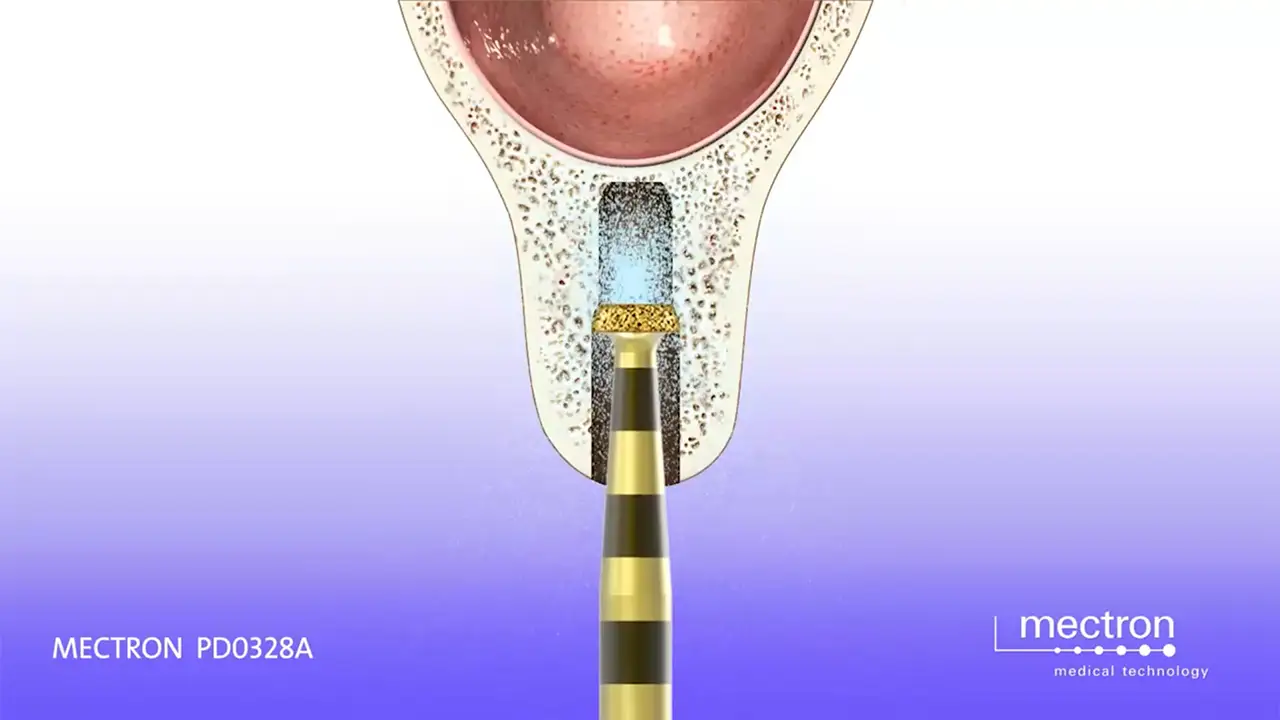

PIEZOSURGERY® Site Preparation with Piezodrill

Mectron – PIEZOSURGERY®

Implant Site Preparation with PiezoDrill